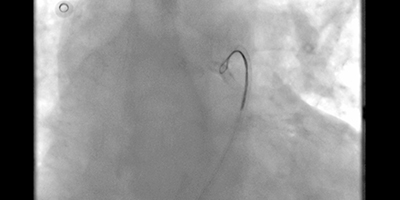

Successful Biventricular Pacemaker Implantation via Right Iliac Vein Route

See Videos